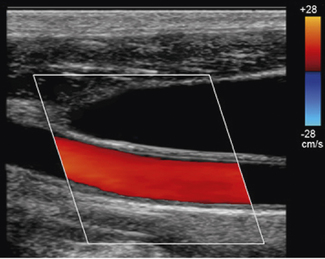

It is probably the first Doppler technique that an operator will utilize to investigate blood flow. Color flow imaging is always used in conjunction with B-mode imaging and once it is activated the operator is presented with a region of interest known as the ‘color box’ and vertical ‘color scale’ bar which are superimposed onto the B-mode image, as illustrated in Figure 11.8.

image

Fig. 11.8 B-mode image with color flow information superimposed. Note that color flow information is only mapped into the color box region. Vertical color scale bar present on the right-hand side of the display

The position and size of this color box can be adjusted to the chosen area of interest by the operator to provide a visual color-coded display or map of blood flow.

For each individual sample volume along each scan line, the average or mean Doppler shifted velocity is calculated. This mean Doppler shifted velocity, which can either be positive or negative, is assigned a color which is then mapped onto a color scale which consists of two primary colors. This is usually red for positive Doppler shifted signals (corresponding to blood flow traveling towards the transducer) and blue for negative Doppler shifted signals (corresponding to blood flow away from the transducer). This typical arrangement can be seen in Figure 11.8.

The color scale is represented as a vertical color bar and normally sits to the side of the B-mode image (see Fig. 11.8). Closer inspection of the color bar shows that it consists of two primary colors with each primary color subdivided into different shades or hues.

Figure 11.10 illustrates a typical color scale bar used. As you can see, it consists of a vertical color bar which is split from the center into two primary colors. The center of a standard color bar scale represents zero or no flow. In this case, blood flow towards the transducer will be labeled red and blood flow away from the transducer is labeled blue. However, in most equipment this color bar scale can be changed, if required, by the operator.

Fig. 11.10 Typical color scale bar. Blood flowing towards the transducer is displayed as RED, blood flowing away from the transducer is BLUE. The brighter shades indicate higher velocities